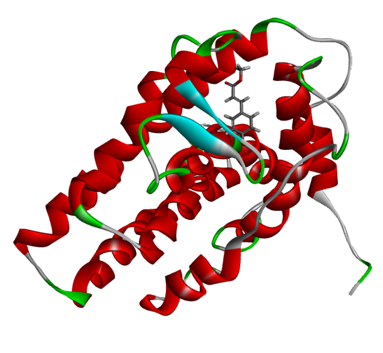

Virtual Screening of Potent Phytochemicals of Murraya paniculata for Anti-Breast Cancer Activity: Molecular Docking and Dynamics Approaches

The Murraya paniculata (MP) methanolic extracts were subjected to Liquid Chromatography-Mass Spectrometry (LC-MS) analysis, a NO assay for measuring antioxidant...Read More